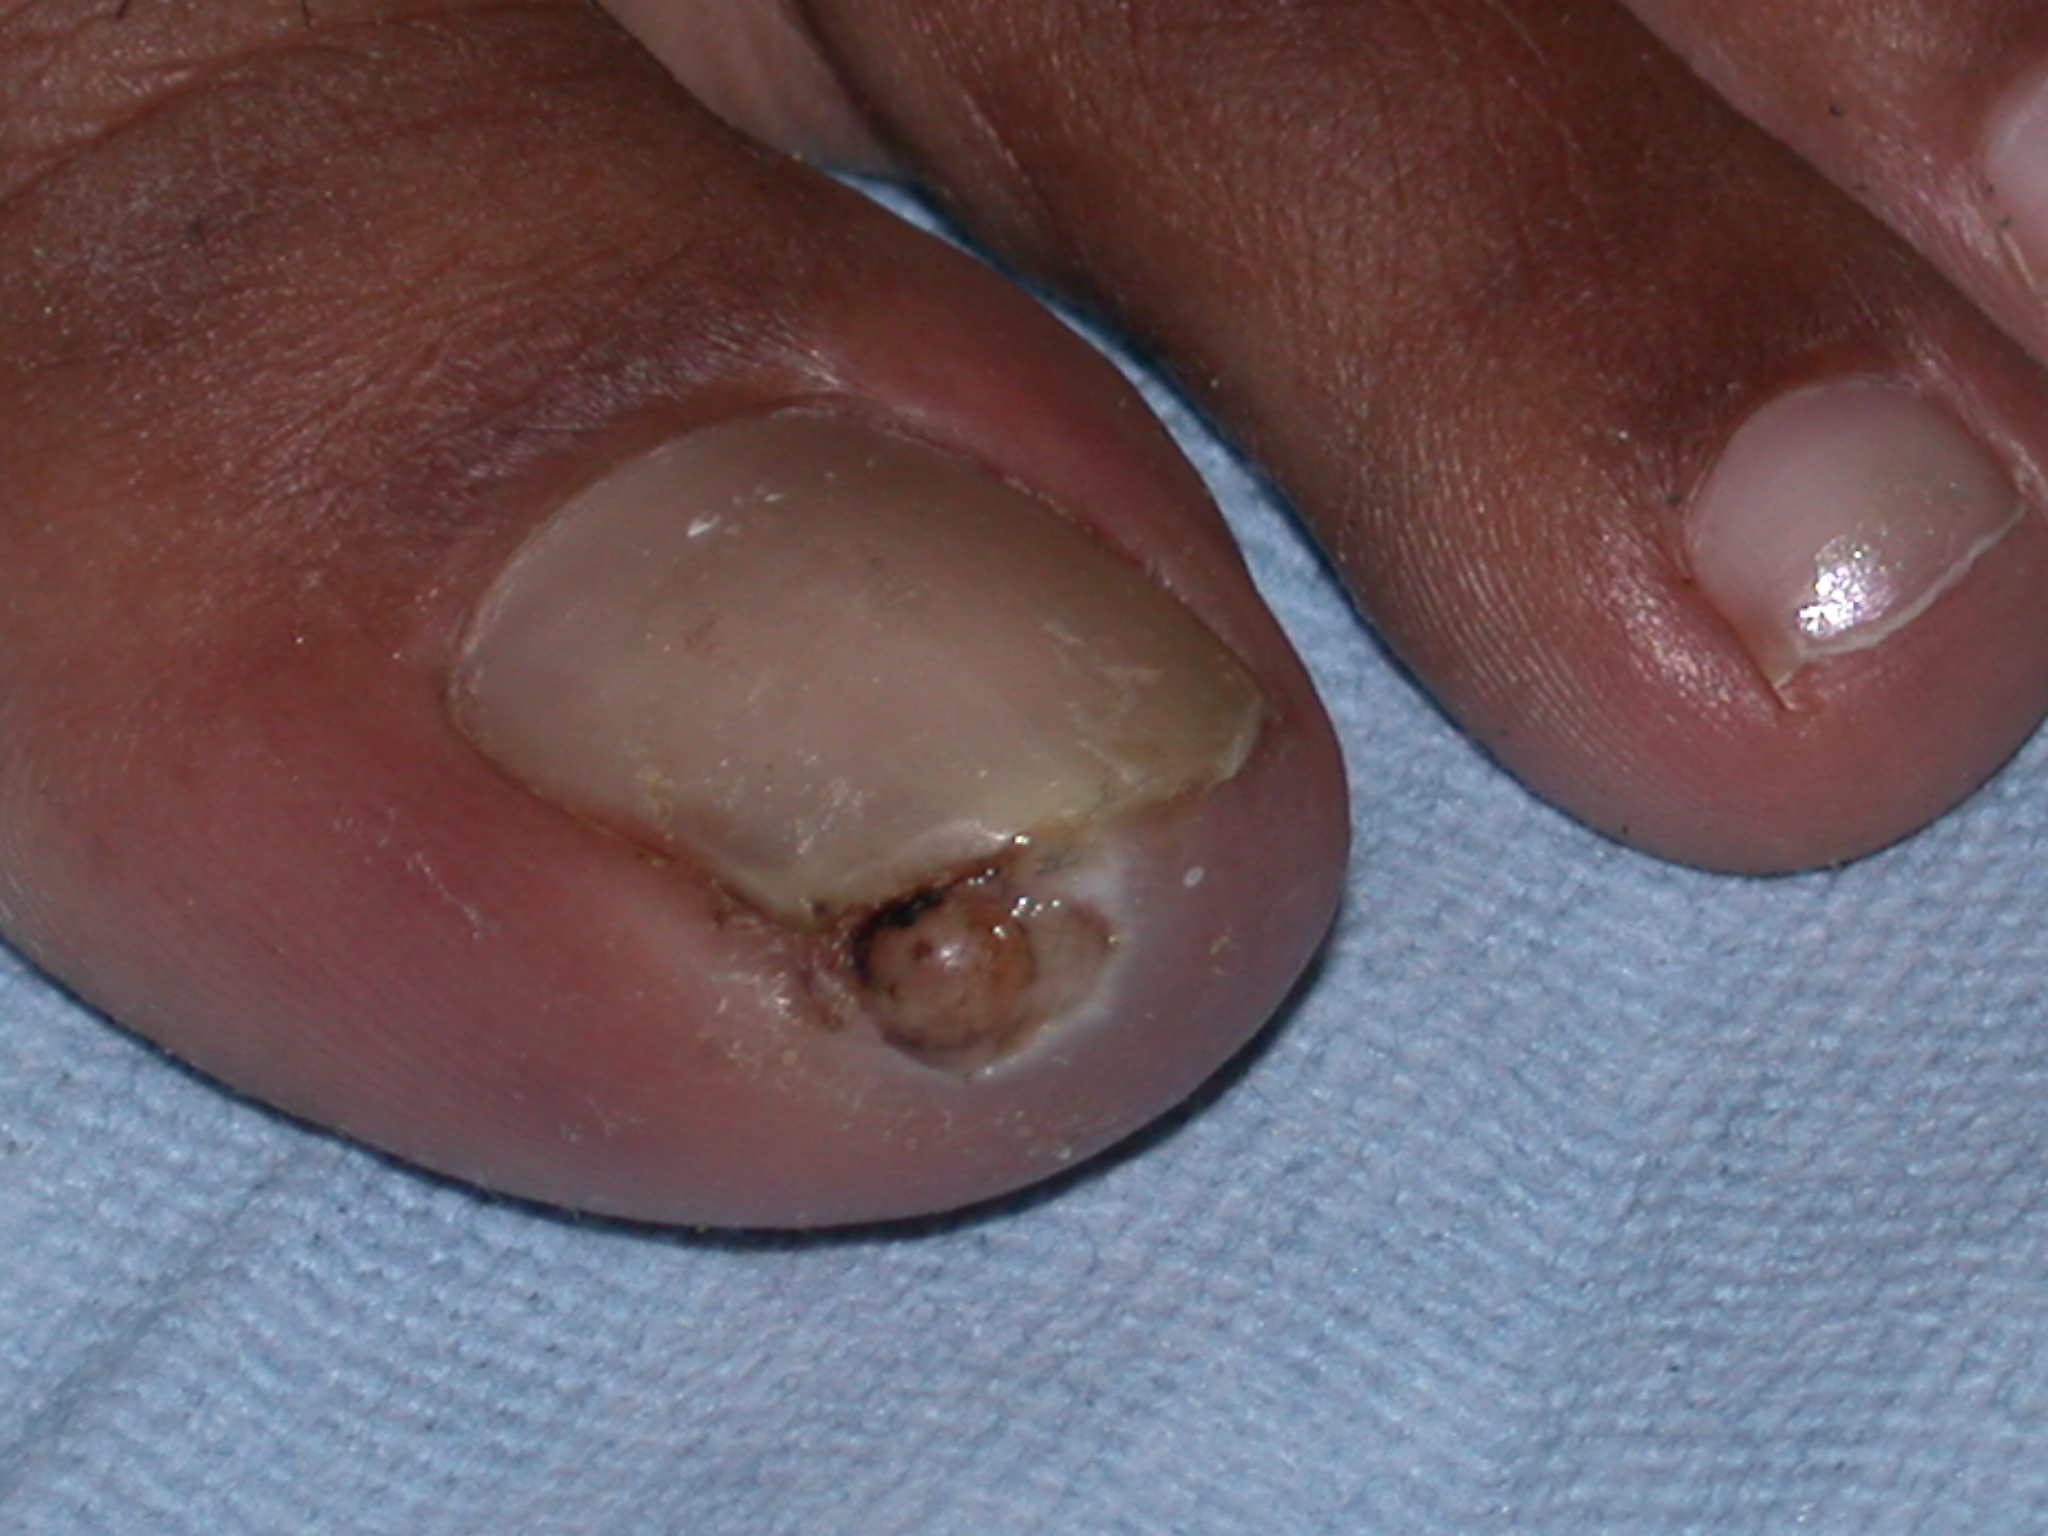

Both the male and the nonfertilized female flea feed intermittently on warm-blooded hosts. Once impregnated, however, the female flea anchors herself to the skin by using biting mouthparts and burrows into the epidermis. Because the process is painless, a keratolytic enzyme may be involved. The flea expands, often reaching 1 cm in diameter. The head is down into the upper dermis feeding from blood vessels, while the caudal tip of the abdomen is at the skin surface, often forming a punctum or an ulceration. The flea breathes through this opening. In many cases, this is described as a white patch with a black dot.

The typical presentation is a nodule (usually on the foot) that slowly enlarges over a few weeks in a patient who has recently been in an endemic area. The nodule can range from 4-10 mm in diameter.